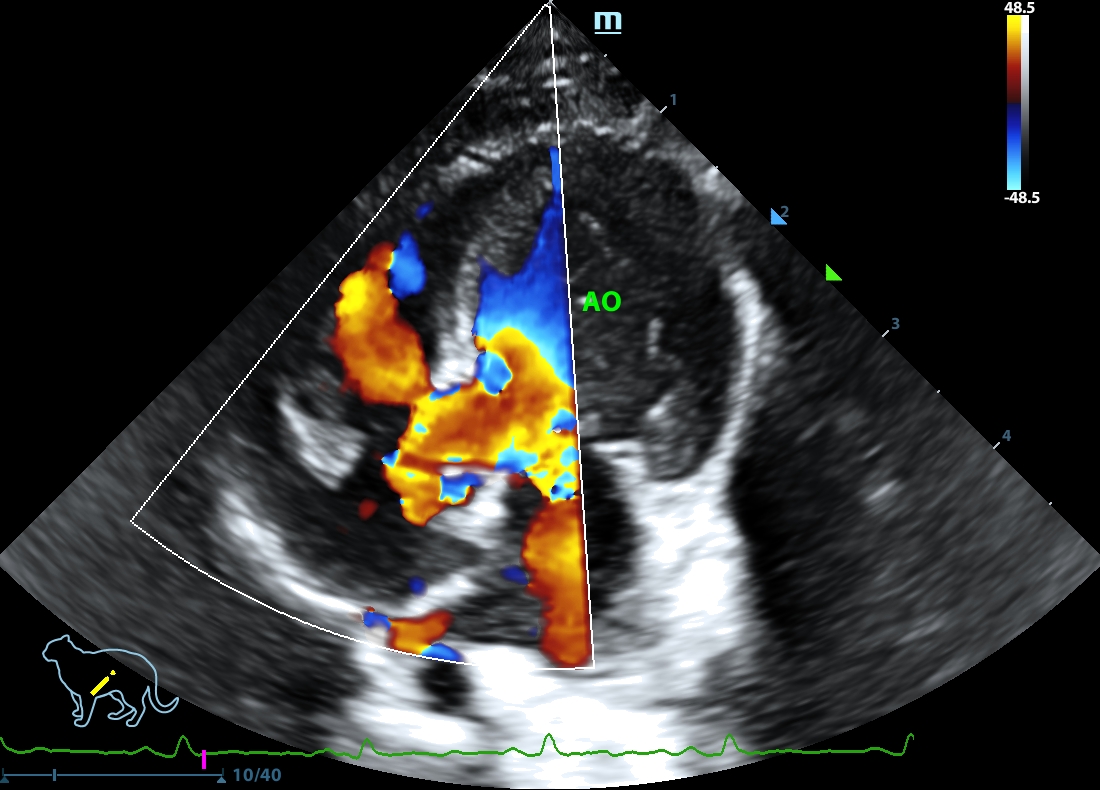

202505170049190155CARD.JPG